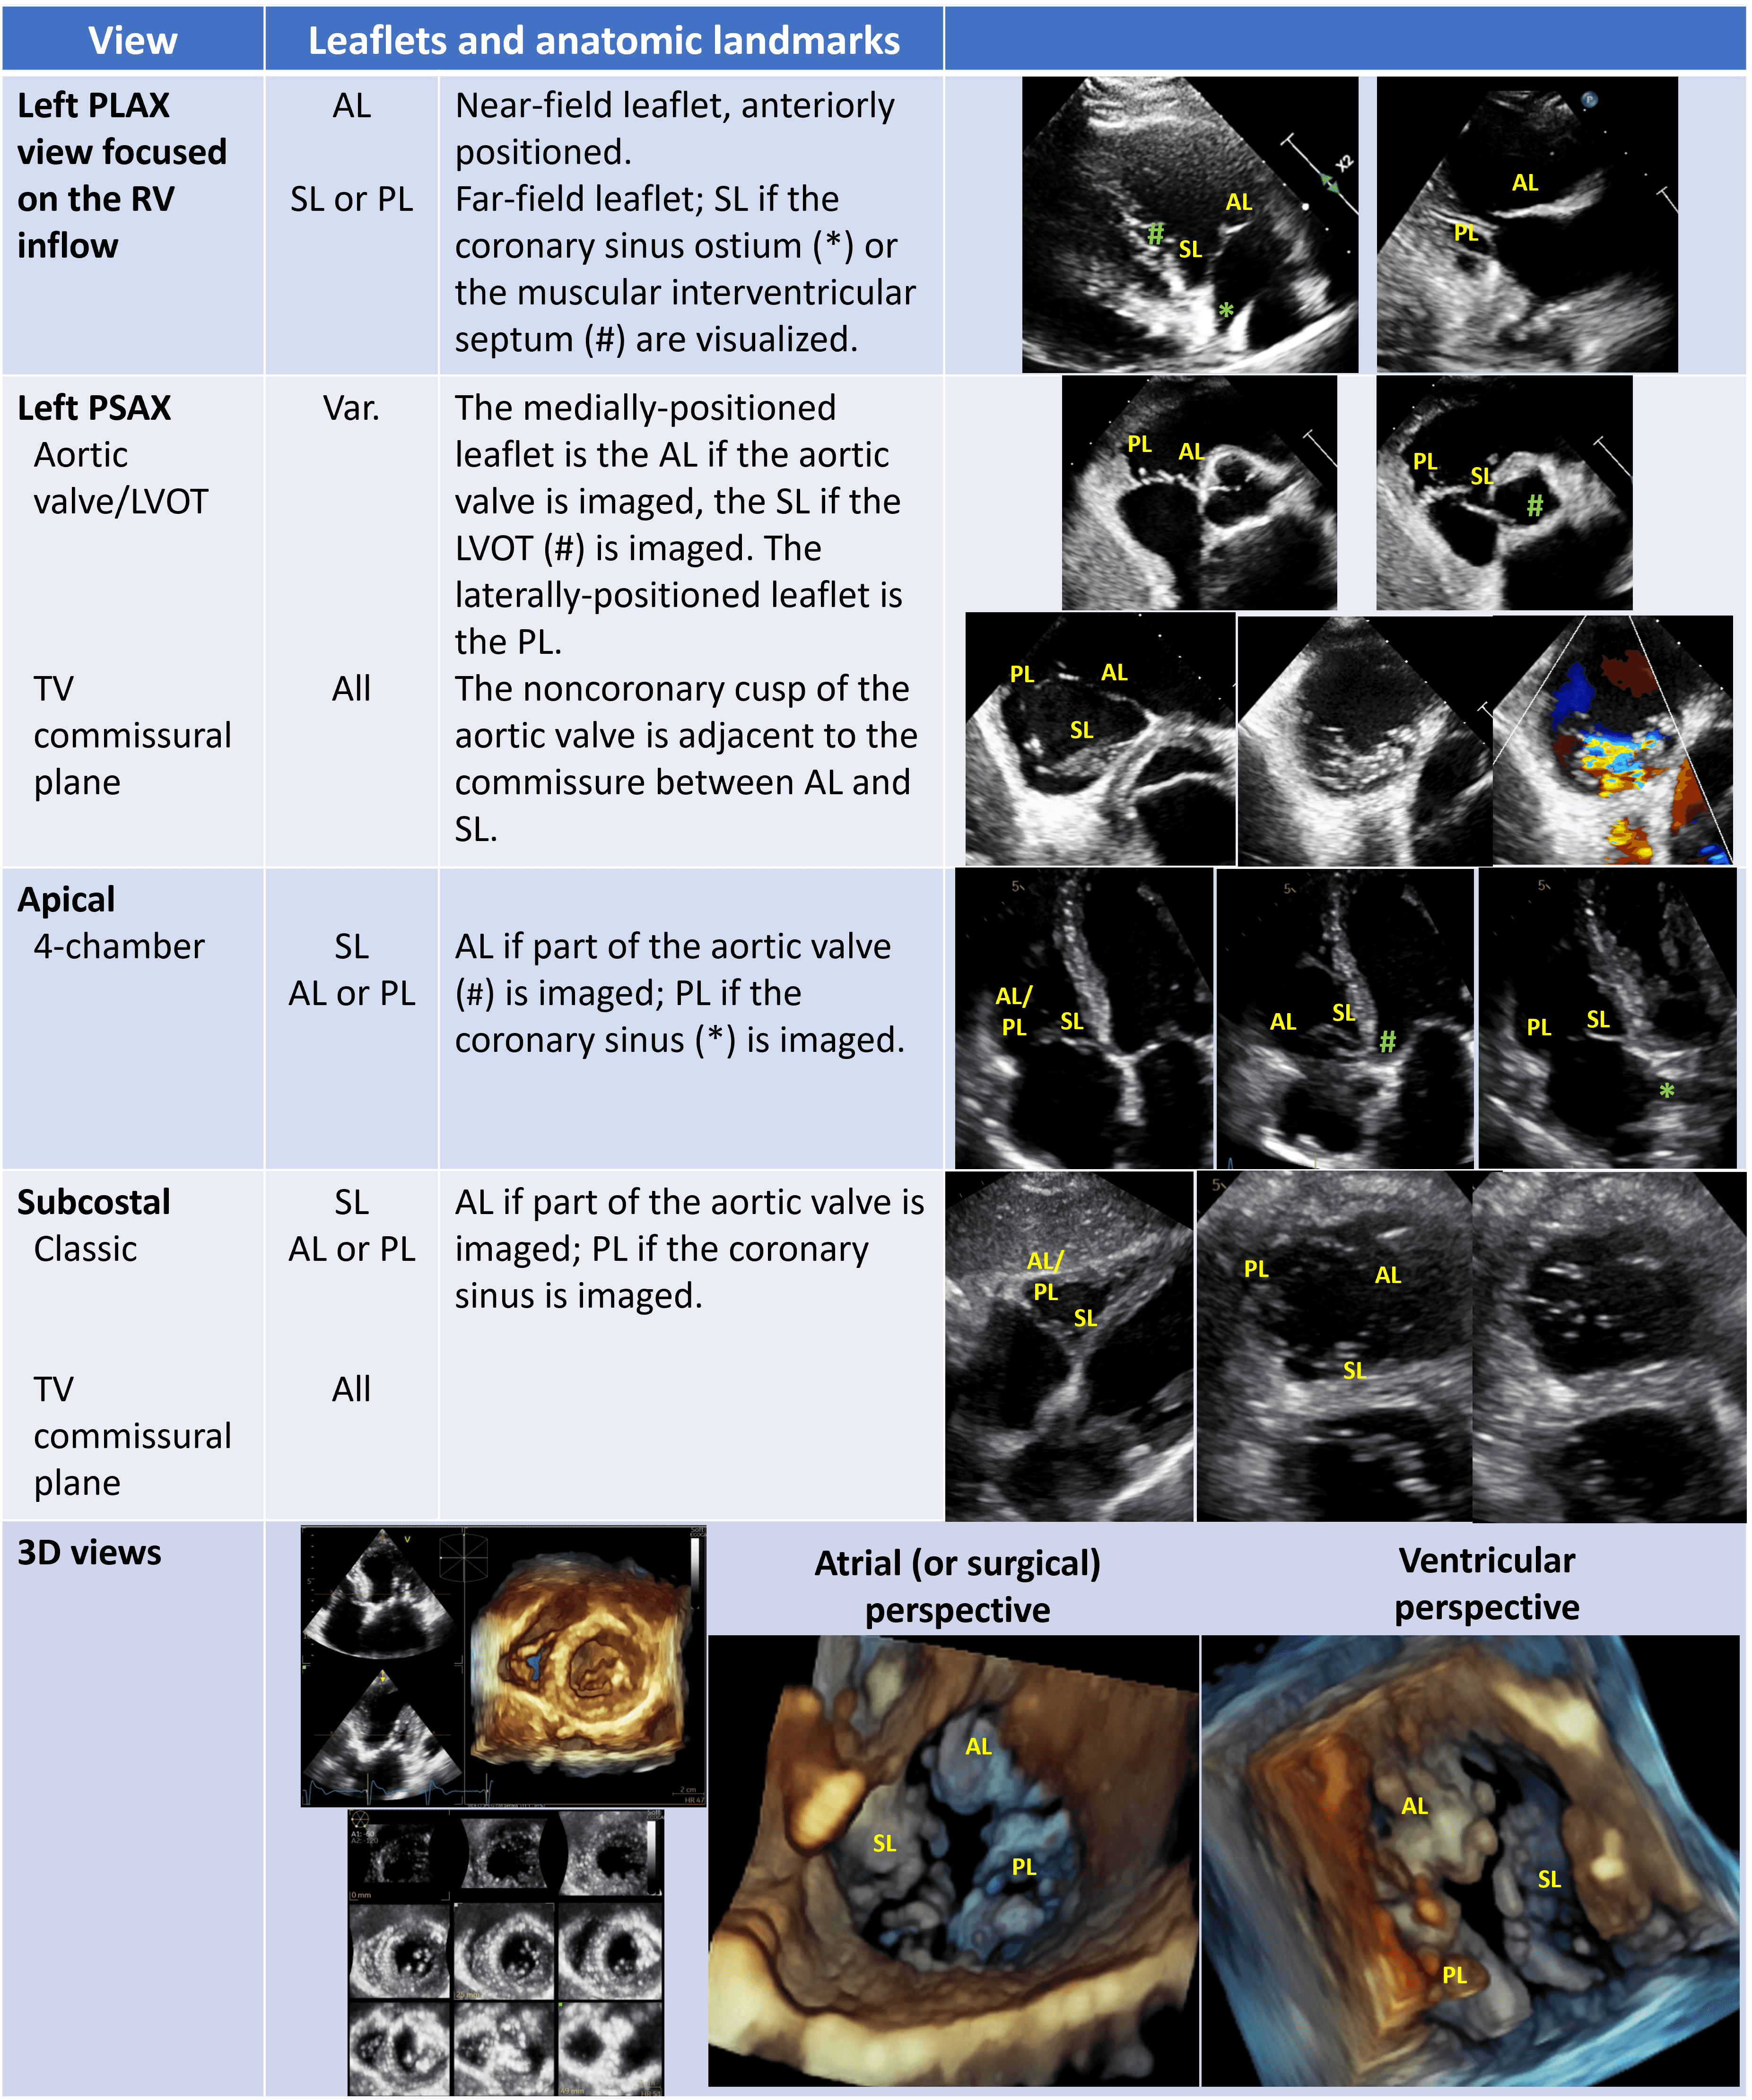

Strength and weakness of each imaging modality are summarized in Table 8.

| Echo | CMR | CT | |

| Anatomical assessment | |||

| TV leaflets | +++ | + | + |

| TV annulus | ++ | + | +++ |

| RH chambers | ++ | +++ | +++ |

| Surrounding structures | + | ++ | +++ |

| Functional assessment | |||

| TR mechanism | +++ | ++ | + |

| TR severity | +++ | +++ | + |

| RV function | ++ | +++ | ++ |

| TTVI procedural planning | |||

| TEER | +++ | + | + |

| Other Device Therapies | ++ | + | +++ |

| Each modality is judged as follows: sufficient (+), good (++) and excellent

(+++). Abbreviations: CMR, cardiac magnetic resonance; CT, computed tomography; RH, right heart; RV, right ventricle; TEER, transcatheter edge-to-edge repair; TR, tricuspid regurgitation; TTVI, transcatheter tricuspid valve intervention; TV, tricuspid valve. | |||